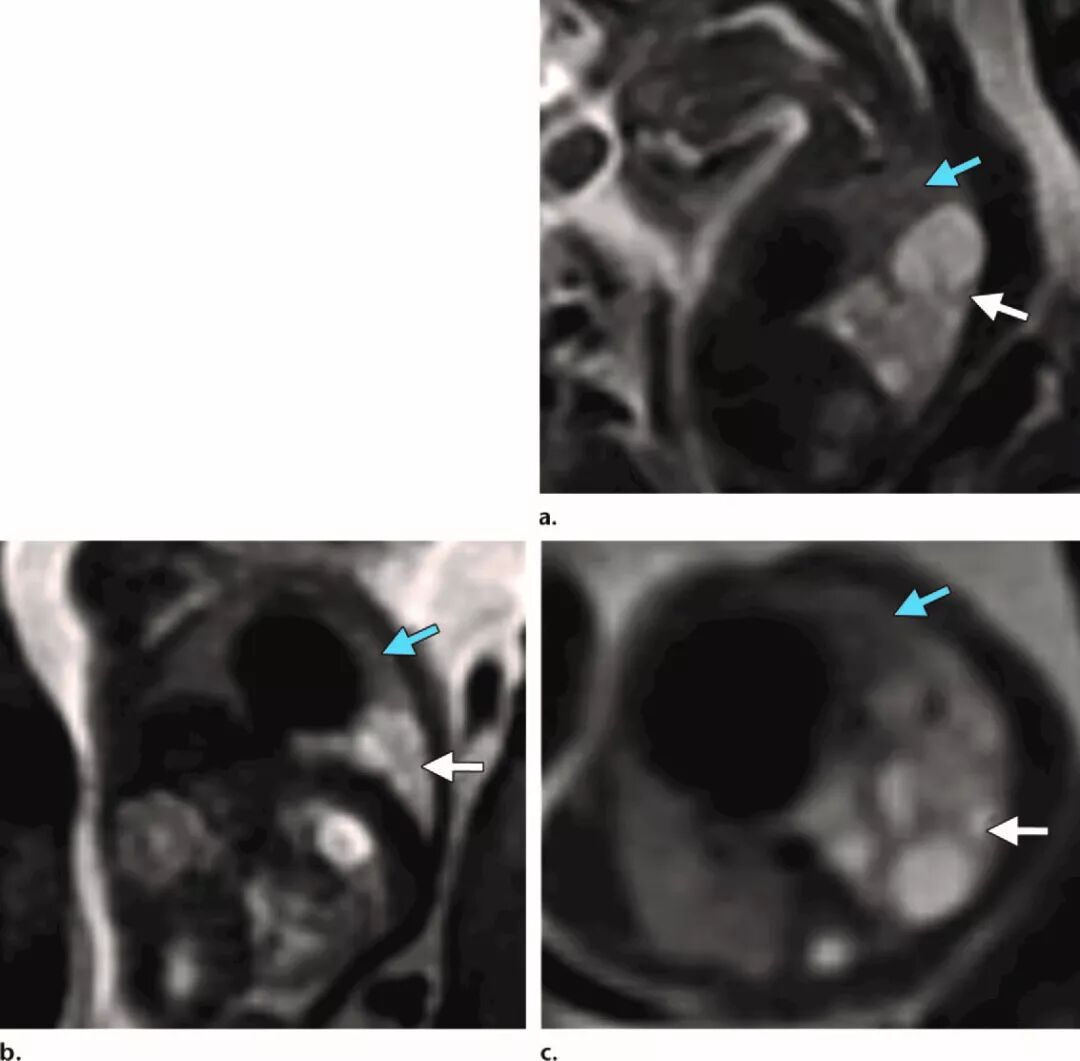

图

5.

Ⅰ型先天性肺腺瘤样畸形(

CCAM

),妊娠

22.5

周。矢状位

(a)

、冠状位

(b)

和轴位

(c)SSFSE T2W

图像,显示一侧肺多囊样病变累及整个左下叶,囊肿大小不一,较大者

>2cm(

白色箭

)

。左上叶

(

蓝色箭

)

由肺裂分隔,与右肺相同,信号正常。

CCAM

相对头围比例(

CCAM volume to head circumference ratio

,

CVR

)为

0.75

,积水发生风险较低

(<3%)

,妊娠

32

周,行

US

检查,发现胎儿肺部

CCAM

受累面积减少。阴道分娩,体重

3200 g

,无需呼吸支持,产后胸部

X

线表现正常。

图

6.

Ⅱ型

CCAM

,妊娠

28

周。矢状位

(a)

、冠状位

(b)

和轴位

(c)SSFSE T2W

图像显示胎儿右肺下叶后段多囊性病变,囊肿

(

箭

)

直径约

0.5-2cm

。